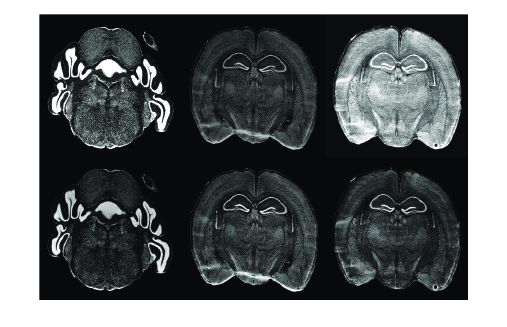

Typically, a 3D volume is reconstructed by registering (aligning) the 2D sections with respect to a chosen reference and stacking successive aligned sections [2]. As the acquisition processes of different 2D histological images are performed independently, slice misalignment and deformation is often unavoidable. Figure 1 shows examples of histological slices with non-cohorent distortions, tears, hole and missing parts. The deformation varies from section to section and non-cohorent distortions may exist in consecutive sections. Choosing an arbitrary slice as a reference slice leads to errors in 3D volume reconstruction, hence, the reference slice should be chosen properly not to contain distortions in order to achive high quality volume reconstruction [3].

Figure 4 shows slices before and after standardization. The first row shows the original data displayed using the default window setting. The second row shows the same slices after standardization displayed using the ”standard” window settings with the parameters defined in Section 5.

![]() |